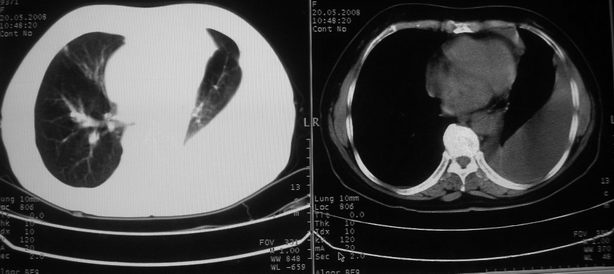

以下是引用w_jianhua在2008-5-22 12:59:00的发言:[br]1.左肺上叶肺癌并左侧胸腔积液可能性大。2不除外支气管内膜结核并包裹性胸腔积液,建议支气管镜检3.左肺下叶肺大泡,肺气肿